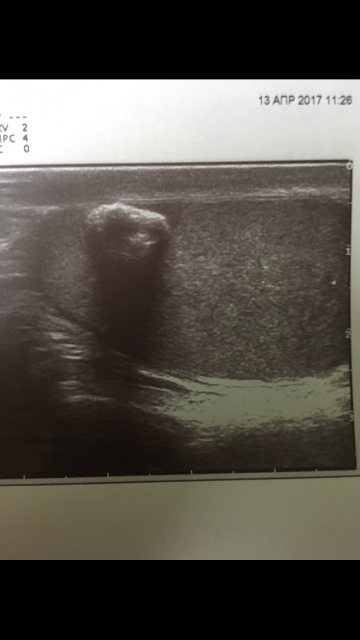

Образование в левом яичке

Выглядит обычным кальцификатом

Или кальцифицированная киста.

Возможно, но маловероятно, для кисты с кальцинированной стенкой больше характерен ровный контур и правильная форма

Согласен, это я покинул для диф.ряда.